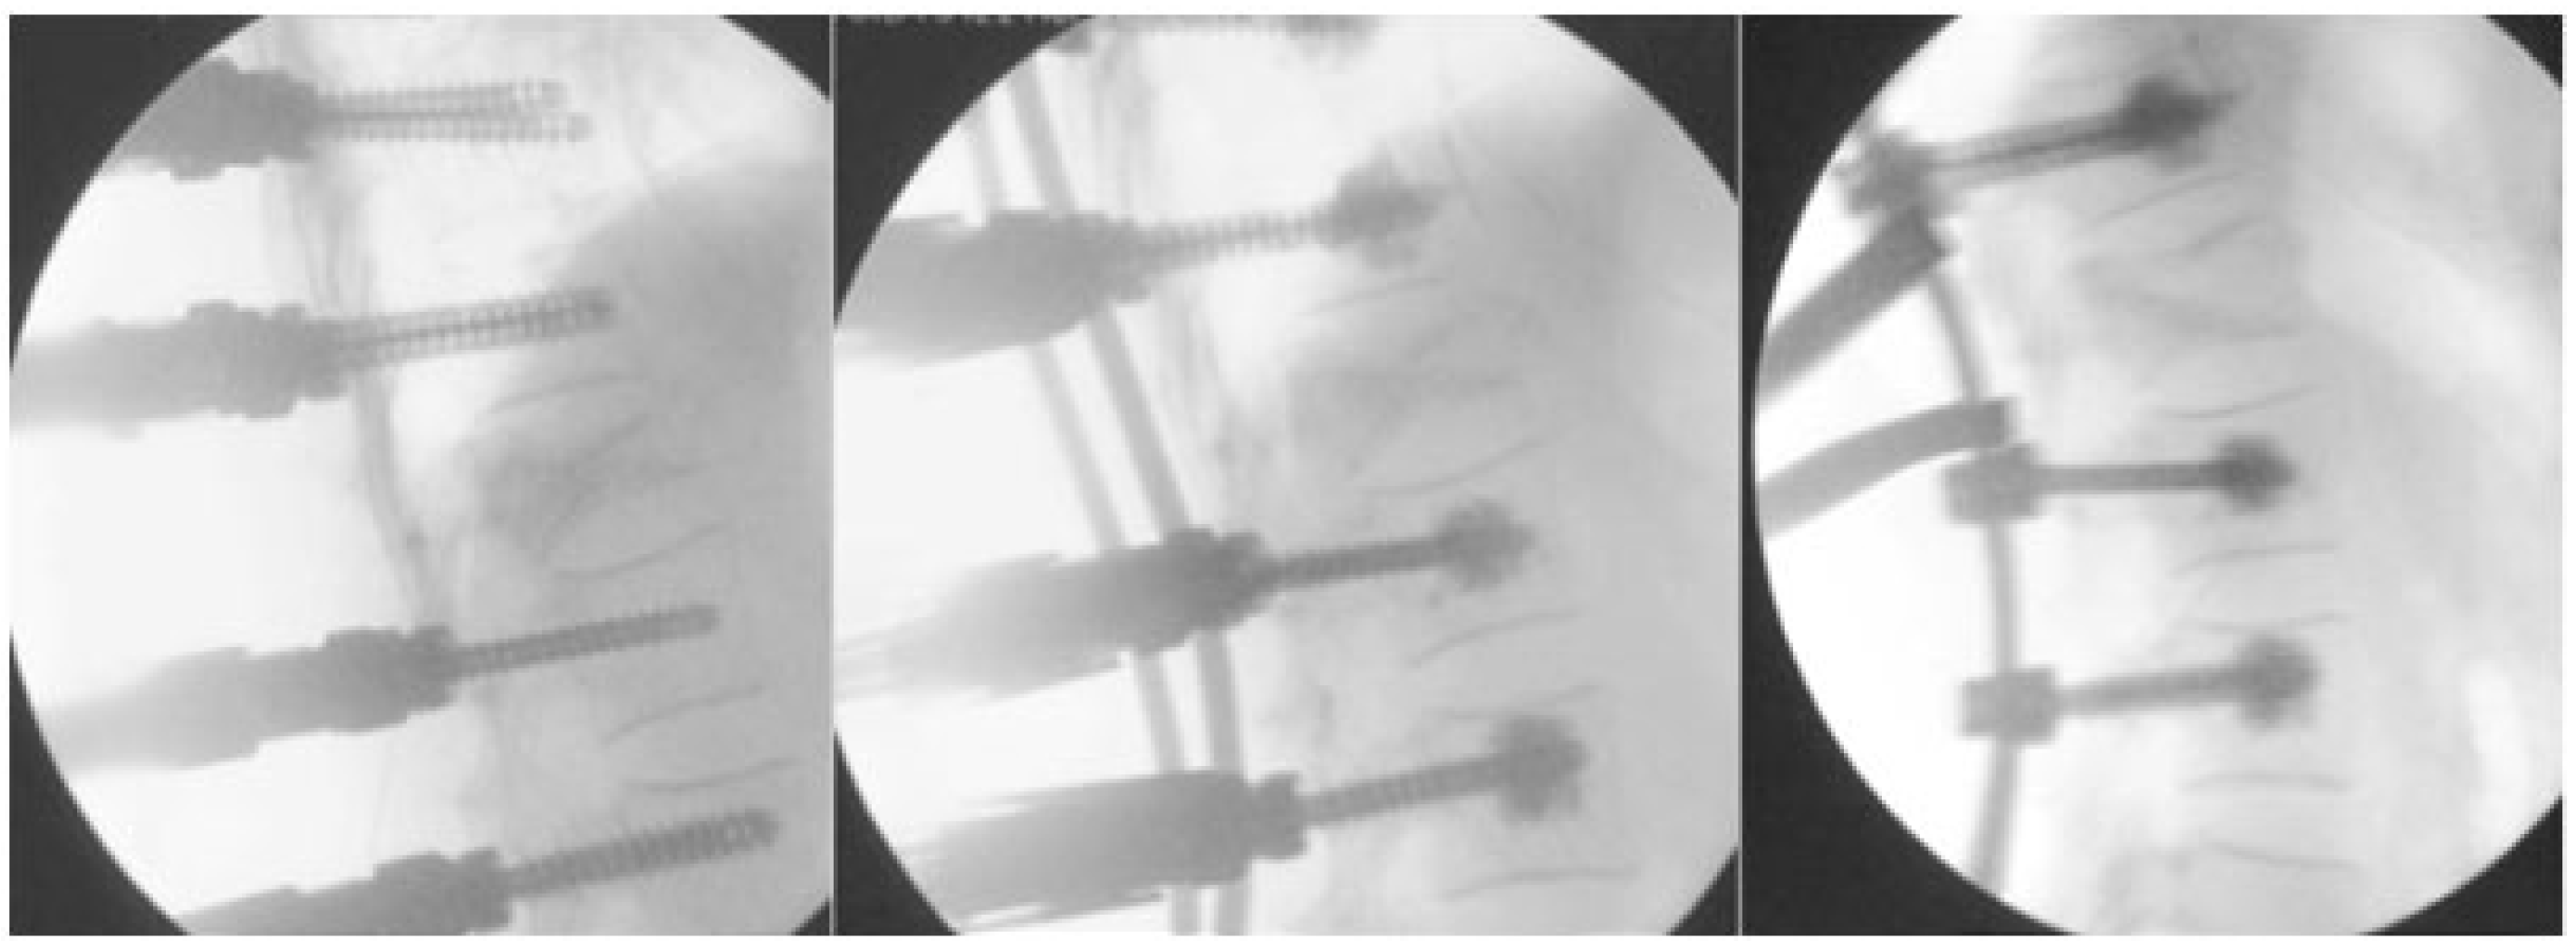

- Optimally reducing pathological fracture. The reduction by osteosynthesis will then allow for optimal vertebro/kyphoplasty.

3.1. Osteosynthesis